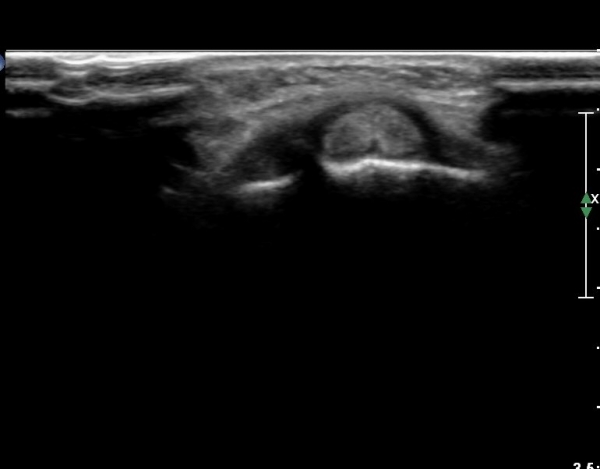

ŽÃËÀÚ¸¦ ¾à°£ ¸»´ÜÀ¸·Î À̵¿ÇÏ´Ï Àå, ´Ü¿äÃø¼ö±Ù½ÅÀü°Ç ºÎÁ¾°ú ÀÌ ½ÅÀü°Ç Ç¥ÃþÀ¸·Î ÁÖÇàÇÏ´Â

À幫Áö½ÅÀü°Ç(EPL)ÀÌ °üÂûµÈ´Ù(»çÁø 4, 5).